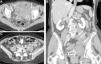

El síndrome de compresión de la vena ilíaca, de May-Thurner o de Cockett es una entidad clínica rara, en la cual la vena ilíaca común izquierda se encuentra comprimida a su paso entre la arteria ilíaca común derecha y la columna. Como consecuencia de la compresión mantenida y del traumatismo causado por la fuerza pulsátil de la arteria sobre la vena, se produce una lesión de la íntima que provoca la formación de membranas o bandas en la luz vascular que dificultan u obstruyen el flujo venoso, lo que favorecería la formación de un trombo. La estrategia terapéutica actual de elección es el tratamiento endovascular con parche venoso y la colocación de endoprótesis, con el objetivo de mejorar el calibre de la luz y permitir un drenaje venoso normal. Presentamos 2 casos clínicos de Síndrome de May-Thurner y revisamos los hallazgos clínicos y radiológicos en la TC computarizada.

Iliac vein compression syndrome (also known as May-Thurner syndrome or Cockett's syndrome) is a rare clinical entity in which the left common iliac vein is compressed when it passes between the right common iliac artery and the spine. The sustained compression and trauma caused by the pulsatile force of the artery on the vein damage the intima and lead to the formation of membranes or bands in the vascular lumen that hinder or obstruct the flow of blood in the vein, favoring thrombus formation. The current treatment strategy of choice is endovascular vein patch angioplasty and stenting with the aim of improving the caliber of the lumen and enabling normal venous drainage. We present two cases of May-Thurner syndrome and review the clinical and CT findings.